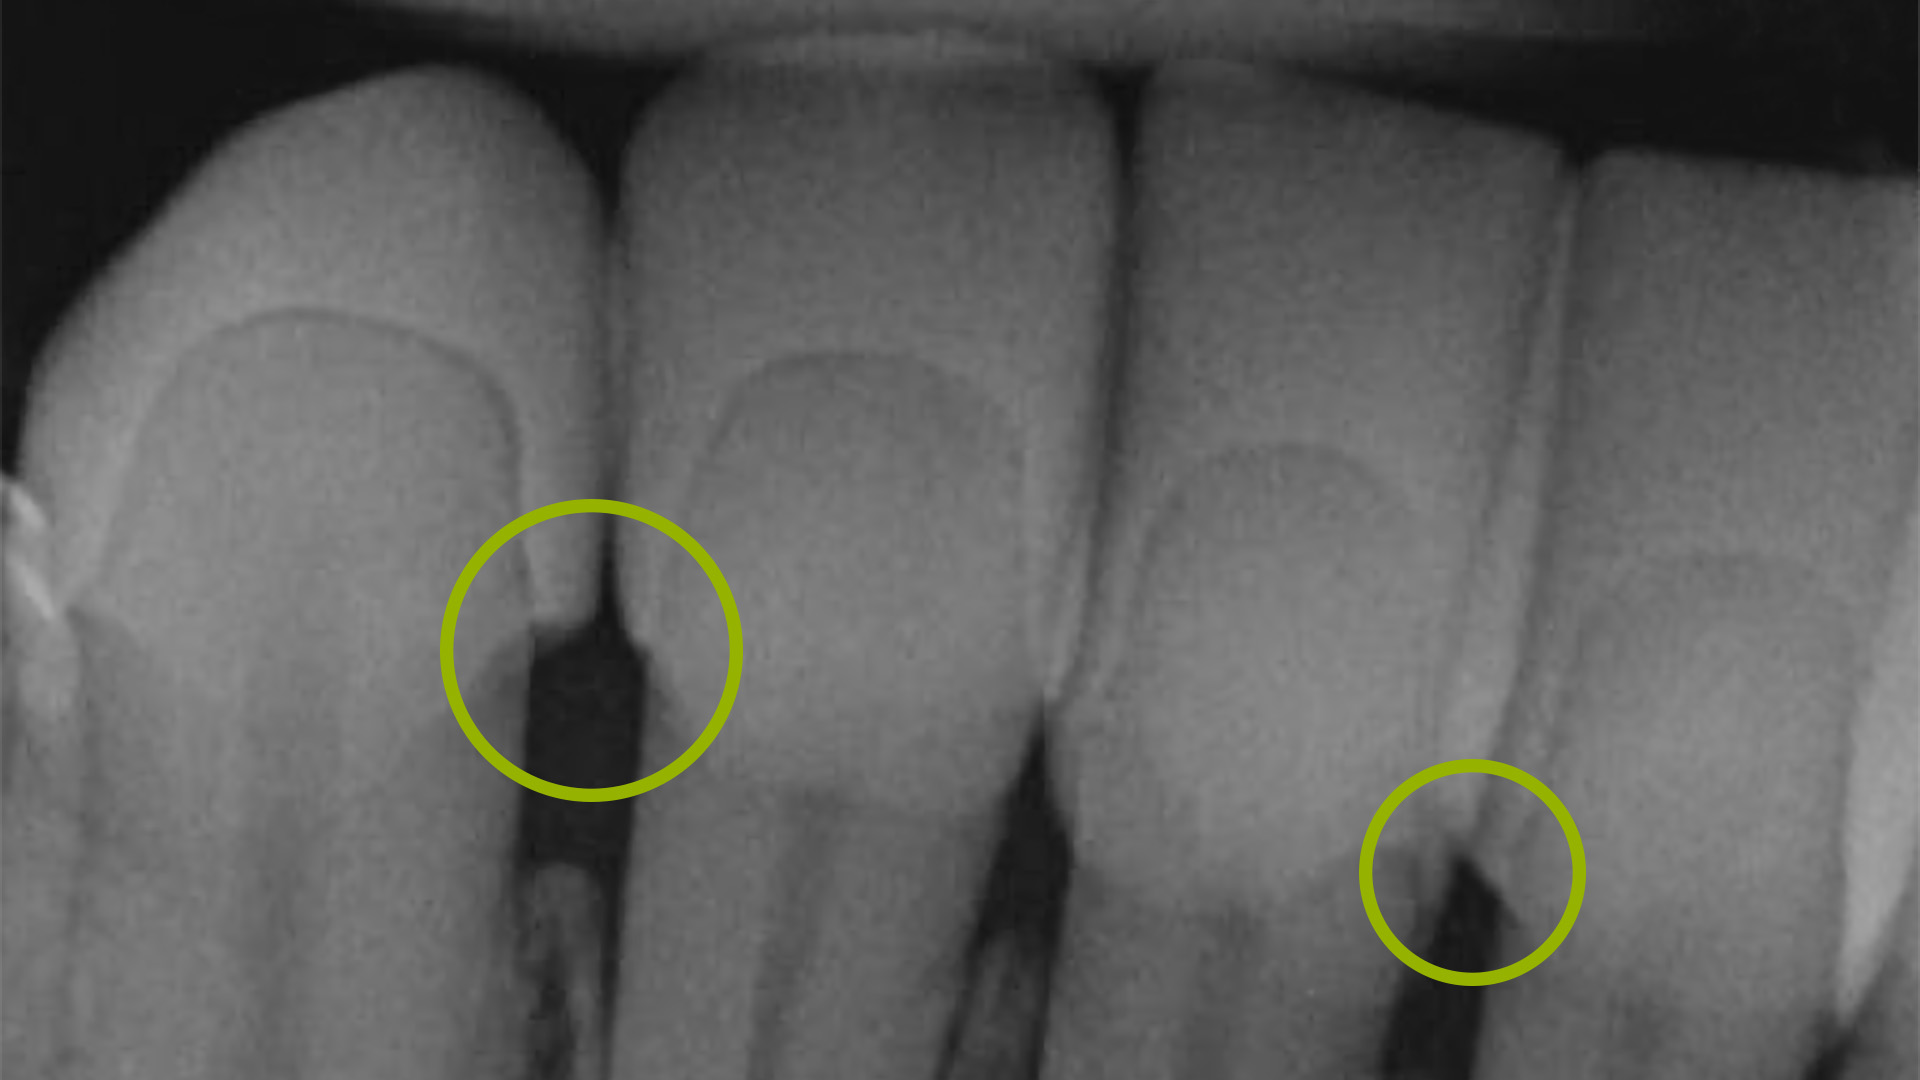

Exmon Basic X-Ray är en röntgensynlig plast som är perfekt för inprovning av alla typer av tandrestaurationer. Detta gör det möjligt att med röntgen kontrollera passformen direkt i patientens mun, vilket bidrar till högre noggrannhet och möjlighet för justeringar i tillverkningsprocessen för den slutgiltiga restaurationen.

Exmon Basic X-Ray